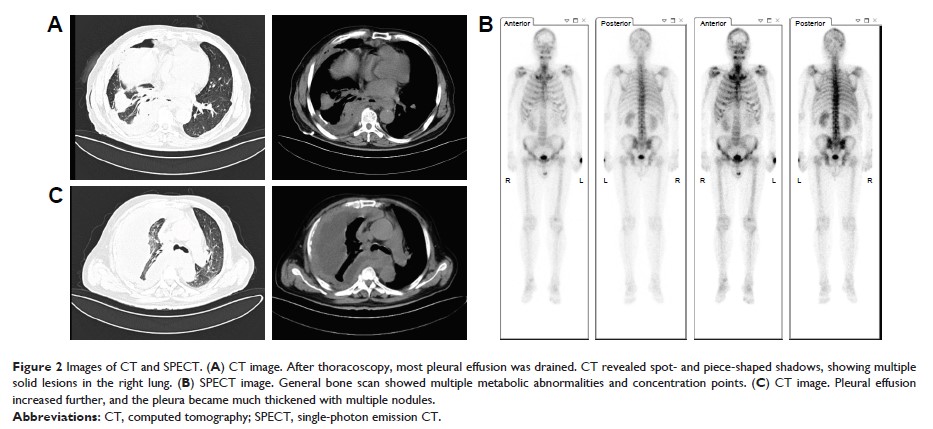

Case Report

- 作者:Fangmin Chen, Qihua Gu, Chengping Hu, Xiaoling Cai, Shuhua Lei

- 期刊:OncoTargets and Therapy